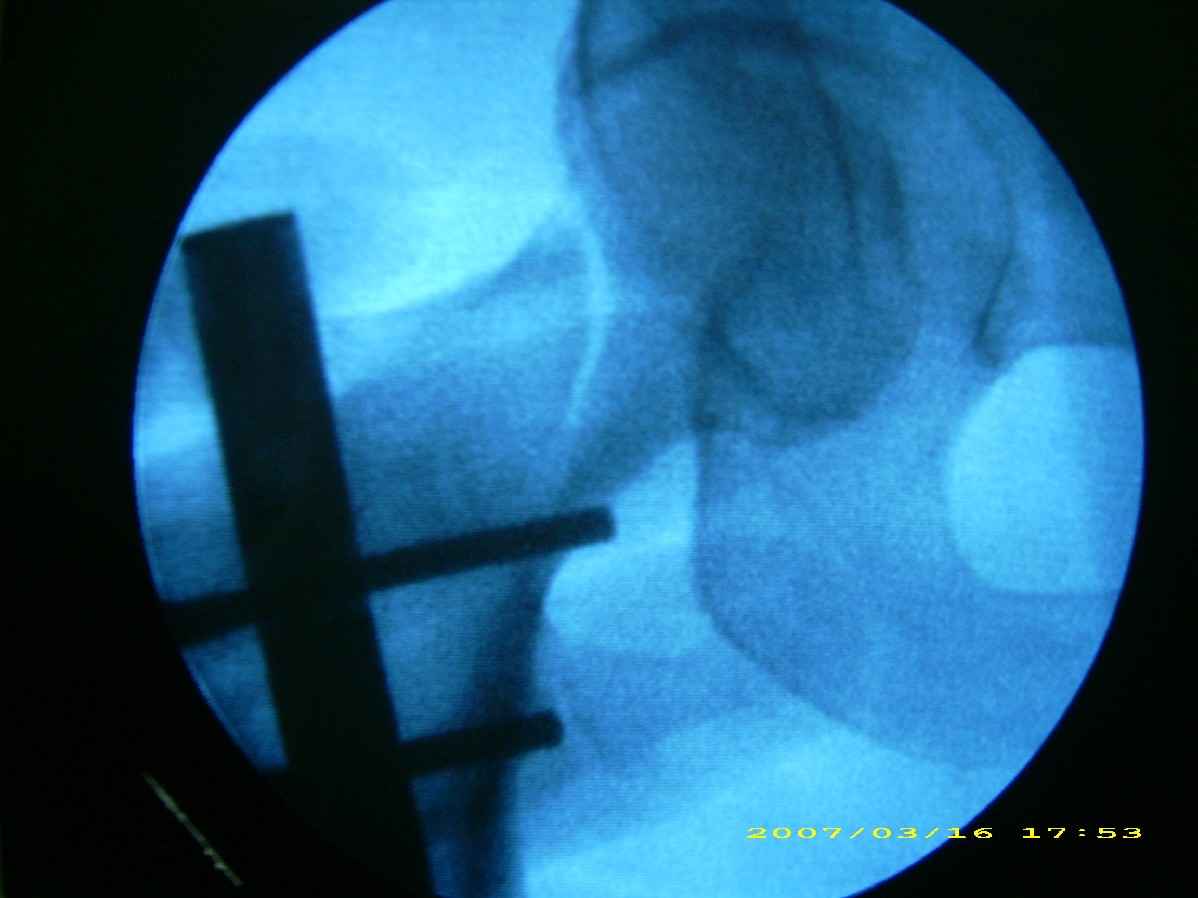

患者,女,因外伤就诊。摄骨盆及右股骨。当时报告骨盆未见明显异常,右股骨中段粉碎性骨折。五天后行股骨中段骨折内固定手术,术中摄床边片示股骨颈骨折。现把术前和术中图像上传。请大家高诊,分析股骨颈骨折是术前漏诊还是其他原因。术前骨盆片右股骨颈显示欠佳是由于股骨中段骨折无法将股骨颈完全显示。

术前片示右股骨颈未见明显骨折征象。如果事先有骨折,由于投照位置原因,骨折线也是完全有可能被挡住重叠而看不见的(并且本例骨折对位良好,更有可能看不到)。所以要凭此判断述前是否有骨折不容易

考虑术前骨折(由于投照位置原因,骨折线有可能被挡住重叠而看不见的或骨折处未有移位可能看不到)。术后由于外力作用骨折线增宽而清楚显示)。